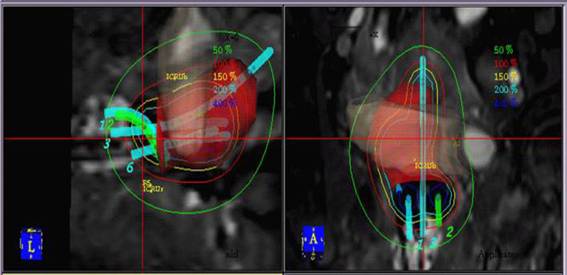

盆腔插植近距离放疗将插植针植入常规后装治疗不能覆盖的肿瘤区域,利用CT 图像的三维后装近距离计划系统, 各插植针可根据CTV 等形态任意排列, 相互间交叉、错位不影响计划的优化, 通过重建各针的三维位置,定义GTV、CTV 及危及器官的位置及受量, 使用逆向治疗计划系统优化各点的驻留时间,从而调节每一点的剂量, 使合成的剂量与治疗的靶区高度适形, 使肿瘤区受到高剂量的精确照射成为可能, 因此,组织间插植引导的近距离放疗联合传统后装放疗具有更为明显的剂量学优势(见图2)。

病例分享:张均华,女,52岁,阴道不规则流血2个月,宫颈活检取病理:鳞状细胞癌。临床诊断:宫颈癌(ⅡA2期),入院后查体:外阴发育正常,阴道通畅,粘膜光滑,宫颈表面见大小约7×7×6cm3菜花样肿物,接触性出血(+),累及阴道前后穹窿,子宫前位,大小及形态正常,分泌物脓血性,量较多,伴恶臭。三合诊:双侧宫旁组织增厚,未达盆壁,弹性尚可,肛门无异常,直肠粘膜光滑,肠腔无狭窄,指套未染血。外照射适形放疗DT5000cGy/25f。三维腔内治疗DT3000cGy/5f(6次),HRCTVD901350cGy,直肠D2cc2510cGy,膀胱D2cc2605cGy。治疗1个月后入院检查:宫颈仍见3×2cm3质硬、固定的残留肿物,给予插植治疗1次 (见图3、4),处方剂量:600cGY,靶区覆盖率达100%,D90=613cGY(90%的体积接受613cGY的照射剂量),危及器官控制在可耐受剂量范围内,1月后评价疗效为CR。